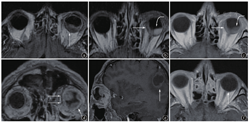

①22例(84.6%)病例为单眼受累,4例(15.4%)为双眼受累(表1)。②14例(53.8%)病例为单发病灶,12例(46.2%)为多发病灶,后者包括8例(66.7%,8/12)单眼多灶,4例(33.3%,4/12)双眼受累(图2)。③部位:位于眼球后极14例(53.8%),后极偏侧9例(34.6%),赤道部3例(11.5%)。④形态:新月形13例(50.0%),半月形2例(7.7%),梭形7例(26.9%),不规则形4例(15.4%)(图3)。⑤边界:病灶内侧缘边界清楚18例(69.2%),模糊8例(30.8%)。⑥最大厚度:2~9mm,平均(4.2±1.8)mm。⑦信号与强化特征:以同层眼肌作为参照,病灶于T1WI呈等信号22例(84.6%),稍高信号4例(15.4%);于T2WI或FLAIR序列呈高或稍高信号17例(65.4%),等信号3例(11.5%),混杂信号6例(23.1%)。增强扫描明显强化16例(61.5%),中等强化8例(30.8%),轻度强化2例(7.7%)。强化均匀19例(73.1%),强化不均匀7例(26.9%)(图4)。

注:患者肺癌病史1.5年,视力下降、视物模糊1周。图a、b为液体衰减反转恢复(FLAIR)序列,见眼球后极椭圆形及新月形多发病灶,呈等或稍高信号(直箭),图c~e为增强T1加权像(T1WI)横断位、冠状位及矢状位。见肿物呈中等强化,冠状位显示病灶为多发(图d),矢状位另可见脑实质内转移灶(图e,直箭)。病灶上方颞侧可见视网膜部分脱离,FLAIR呈高信号,增强扫描未见强化(图b、c,弯箭)。图f为化疗6个周期后复查,脉络膜转移瘤病灶完全消失。